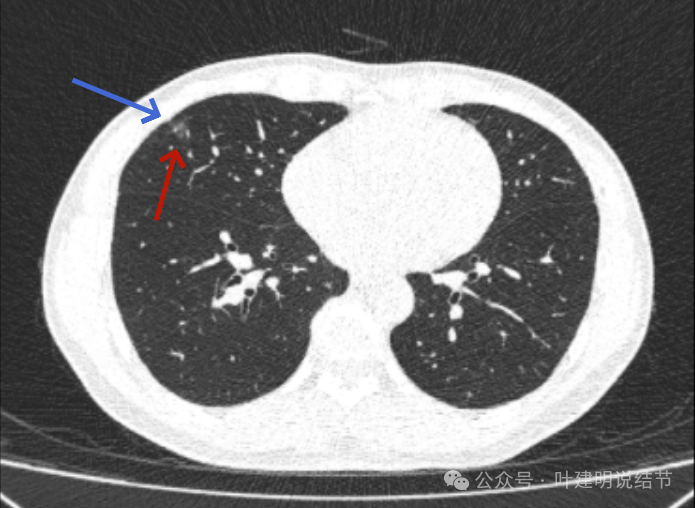

2023年10月时病灶又有进展,表面有细毛刺、灶内血管明显异常增粗,中间仍有小的空泡征,整体轮廓与边界清,大小也有所增大。磨玻璃部分的密度也较之前有所增加。